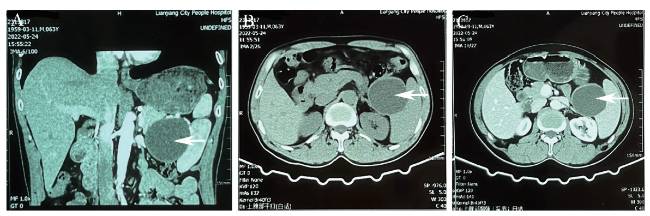

1个月后患者返院复查腹部MRI,胰腺尾部见类圆形T1WI低信号影,T2WI高信号影,DWI呈稍高信号,内壁光滑,增强扫描未见强化,考虑胰腺尾部囊性占位,良性病变以假性囊肿可能性大(图3)。患者为进一步治疗,入住我院肝胆外科,有手术指征并与患者及家属沟通后于全身麻醉下行腹腔镜胰体尾切除术+脾切除术+腹腔粘连松解,术中见胰尾处有一大小7.0 cm×8.0 cm的囊性肿物,包膜完整,质韧,活动度可,肿物与脾动静脉、主胰管间距约0.5 cm以上,其余胰腺部分质地软,胰腺周围、脾动脉淋巴结及脾门淋巴结部分未见肿大。术后病理结果:囊壁由纤维组织构成,内壁大部分区域未见被覆上皮,局部被覆鳞状上皮,囊壁内见较多淋巴细胞浸润,局部淋巴滤泡形成(图4)。最后诊断为PLEC。

图3 一例PLEC患者腹部MRI图

注:A为MRI平扫冠状位图片,胰腺尾部见类圆形T1WI低信号影,T2WI高信号影,DWI呈稍高信号,内壁光滑;B为MRI平扫横断位图片;C为MRI增强扫描横断位图片,未见强化;白色箭头所示为低密度影。